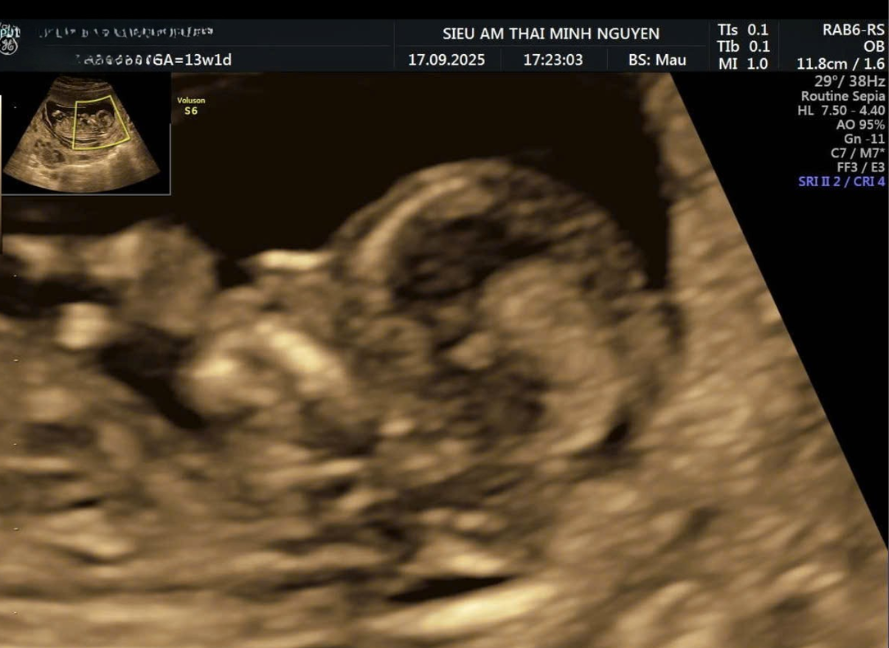

Bất sản xương mũi là tình trạng không thấy hình ảnh xương mũi trên mặt cắt dọc giữa khuôn mặt thai nhi khi siêu âm. Ở thai bình thường, xương mũi thai nhi xuất hiện như một đường tăng âm sáng song song với da. Khi không thấy đường tăng âm này, bác sĩ có thể ghi nhận bất sản hoặc không thấy xương mũi.

Tình trạng này thường được phát hiện ở siêu âm 12 tuần, giai đoạn sàng lọc bất thường nhiễm sắc thể.

Trong quá trình phát triển, xương mũi thai nhi được cốt hóa dần từ tam cá nguyệt đầu.

Ở thai mắc trisomy 21, tỷ lệ không thấy xương mũi ở tuần 11–13 cao hơn so với thai bình thường. Vì vậy, bất sản xương mũi được xem là một dấu hiệu mềm gợi ý nguy cơ hội chứng Down.

Tuy nhiên, đây không phải là chẩn đoán xác định. Một tỷ lệ nhỏ thai bình thường vẫn có thể không thấy xương mũi ở giai đoạn sớm.